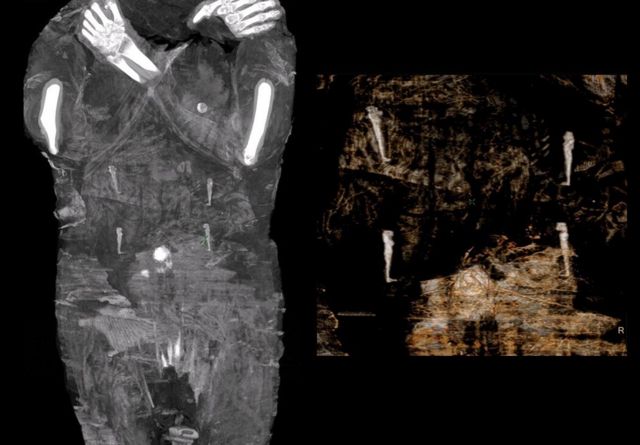

پولینڈ کے سائنس دانوں کی ایک ٹیم کا کہنا ہے کہ انھوں نے ایک حنوط شدہ حاملہ مصری ممی دریافت کی ہے۔ یہ اپنی طرز کی واحد دریافت ہے۔

پہلے خیال تھا کہ یہ کسی مرد پجاری کی ممی ہے لیکن سکین سے پتہ چلا کہ یہ کسی عورت کی ممی ہے جو حمل کے آخری مراحل میں تھی۔

جرنل میں چھپنے والے مضمون میں انھوں نے اپنی دریافت کا اعلان کرتے ہوئے لکھا کہ ’پیش ہے ایک حنوط شدہ حاملہ عورت کی ممی کی پہلی مثال اور اس طرح کے جنین کی پہلی ریڈیولوجیکل تصاویر۔‘

جنین کے سر کے گھیرے سے انھوں اندازہ لگایا کہ جب ماں کی موت نامعلوم وجوہات کی بنا پر ہوئی تو اس وقت اس کی عمر 26 اور 30 ہفتوں کے درمیان ہو گی۔

محققین نے اس کام کے لیے سی ٹی سکینر اور ریڈیولوگسٹس کی مدد حاصل کی

ماں کے پیٹ کے اندر سے چار بنڈل نکلے جن میں خیال ہے کہ اعضا کو حنوط کر کے رکھا گیا تھا، لیکن سائنس دانوں کا کہنا ہے کہ جنین کو بچہ دانی سے نہیں ہٹایا گیا تھا۔